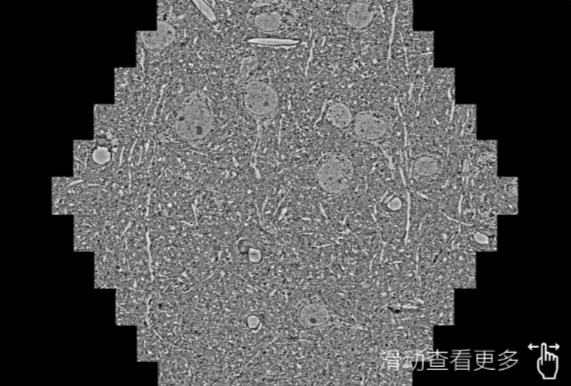

鼠脑切片。左图使用三沙蔡司三沙扫描电镜MultiSEM706对165μmx143pm面积区域成像,耗时仅需1.5秒。右图为鼠脑切片中30μm区域放大效果。样品由芝加哥大学B.Kasthuri提供。

使用蔡司高速三沙扫描电镜MultiSEM对1mm²人脑皮层组织进行高分辨成像,并对其中的各种细胞结构进行三维重构分析。左图展示了2x3mm²组织平面中锥体神经元的三维重构效果。右图显示了局部体积神经元三维重构。图像由哈佛大学chtman实验室提供,渲染图由D. Berger 制作。